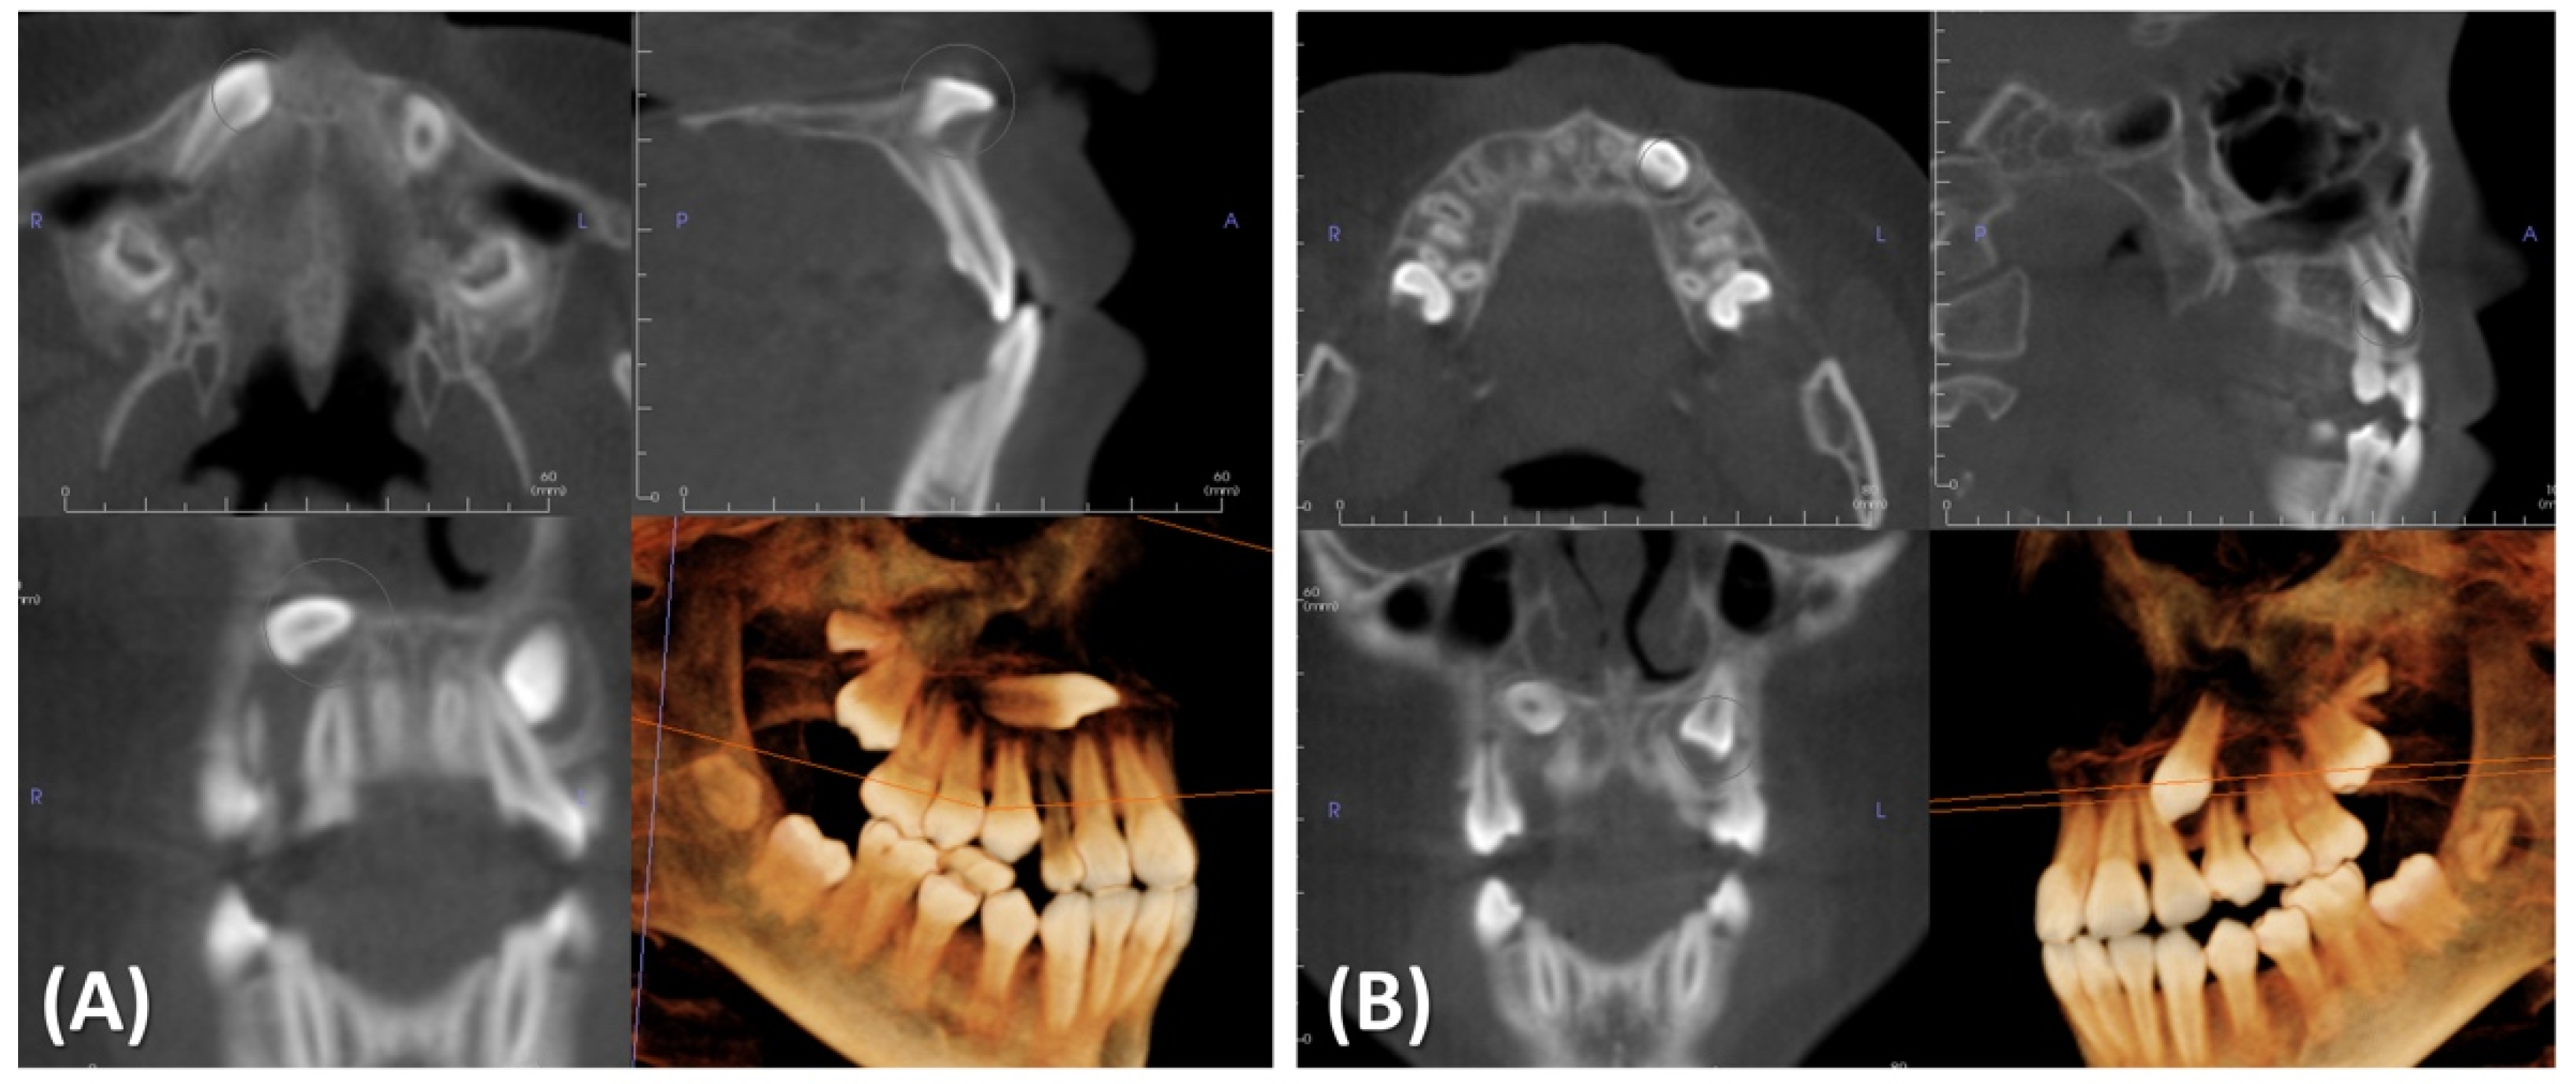

2. Case Presentation

2.1. Diagnosis and Etiology